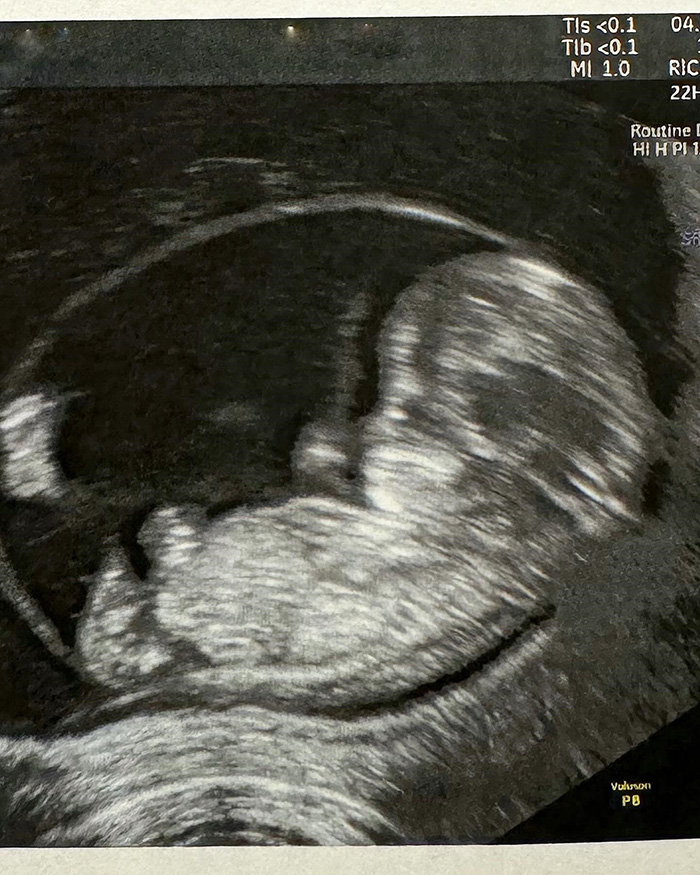

"ถึงเวลาที่พอจะบอกทุกคนได้แล้วค่ะ ช่วงเกือบ 2 เดือนที่ผ่านมาที่ไม่ได้ไปอ่านข่าวใส่ไข่และตลาดสด เพราะว่าต้องดูแลลูก ทั้งน้องคิดและประคองอีกหนึ่งชีวิตในท้อง เนื่องจากรถเมล์มีภาวะแท้งคุกคาม เย็นนี้จะกลับไปอ่านข่าวแล้วค่ะไว้จะเล่าให้ฟังในข่าวใส่ไข่นะคะ Soon to be family o f4. KIDD leveled up to big brother"

ก่อนที่ใน IG polyplus_jad_hai จะมีรายงานเกี่ยวกับเรื่องนี้ว่า รถเมล์ คะนึงนิจ ได้เปิดใจเล่าถึงภาวะแท้งคุกคามที่เกิดขึ้น คือมาทำงานแล้วมีเลือดไหลออกมา จึงได้ไปตรวจ หมอให้อยู่นิ่ง ๆ เพื่อไม่ให้มดลูกบีบตัวเยอะ ต้องนอนอยู่บนเตียงเฉย ๆ ตอนนั้น 50/50 คุณหมอบอกต้องทำใจ กลัวจะหลุด โชคดีน้องพยายามเกาะแน่น ส่วนตอนนี้ปลอดภัยแล้ว